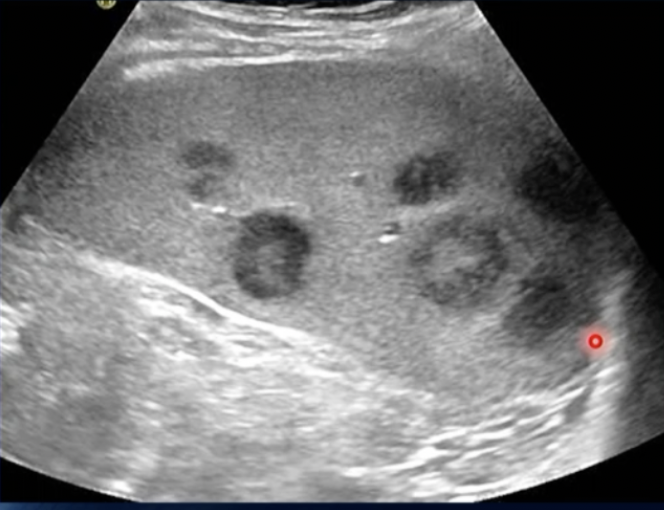

Label + Which is Long/TRV

Long then Trv